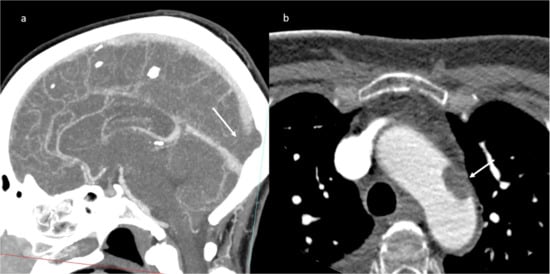

An abdomen angio-CT showed filling defects at the level of left portal branch (Figure 7) and at the level of right suprahepatic vein (7). Bilaterally, it was adrenal hemorrhage (Figure 8) and blood in the pelvis.

Figure 7.

CT scan; in (a) MPR (arrow shows thrombosis of the left portal branch) and in (b) axial plain during portal phase arrow shows thrombosis if the right (Figuer suprahepatic vein).